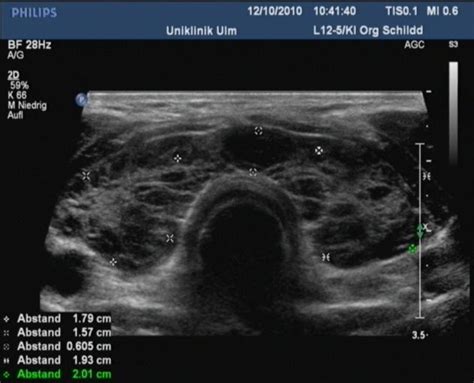

Schilddrüsenknoten: Eine häufige, aber oft harmlose Veränderung

Schilddrüsenknoten sind in Deutschland sehr verbreitet. Schätzungen zufolge haben etwa 25% der Erwachsenen solche Veränderungen in der Schilddrüse. Hauptursache hierfür war lange Zeit der Jodmangel, der sich durch die Verwendung von jodiertem Speisesalz in den letzten Jahren verbessert hat.

Schilddrüsenknoten sind meist gutartig und verursachen selten Beschwerden. Erst wenn sie sehr groß werden, können sie Druckgefühle oder Schluckbeschwerden auslösen. Die Hormonwerte (TSH, fT3, fT4) sind bei Schilddrüsenknoten fast immer normal.

"Heiße" und "kalte" Knoten

- "Heiße Knoten" produzieren selbstständig Schilddrüsenhormone und können so eine Schilddrüsenüberfunktion (Autonomie) verursachen. Dies zeigt sich in einem absinkenden TSH-Wert. Eine plötzliche Jodzufuhr (z.B. durch Röntgenkontrastmittel) kann bei vorbestehenden "heißen" Knoten eine Überfunktion auslösen.

- "Kalte Knoten" weisen einen verminderten oder fehlenden Schilddrüsenstoffwechsel auf und werden im Szintigramm (einer nuklearmedizinischen Untersuchung) sichtbar. Nur etwa 2% der kalten Knoten sind bösartig.

Eine Behandlung von Schilddrüsenknoten ist nur in seltenen Fällen notwendig, z.B. bei Verdacht auf Bösartigkeit, bei Verdrängungserscheinungen oder starken Beschwerden. Eine medikamentöse Behandlung mit Jod und/oder Schilddrüsenhormonen kann bei gutartigen Knoten erwogen werden, insbesondere wenn ein Jodmangel vorliegt.